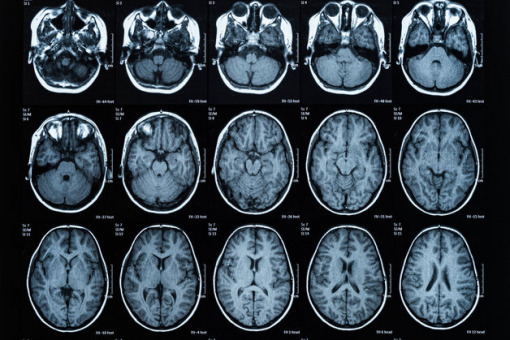

Naukowcy z Ohio State University (USA) przeprowadzili badanie z udziałem 174 zdrowych dorosłych. Uczestnikom wykonano skany mózgów za pomocą fMRI (funkcjonalnego rezonansu magnetycznego).

Do analizy wykonanych wcześniej skanów naukowcy wykorzystali najnowocześniejsze techniki sztucznej inteligencji i moc obliczeniową uczelnianego superkomputera. Korelacje między obrazami z fMRI a oświadczeniami uczestników co do ich poglądów określano w sześciostopniowej skali: od bardzo liberalnych do bardzo konserwatywnych.